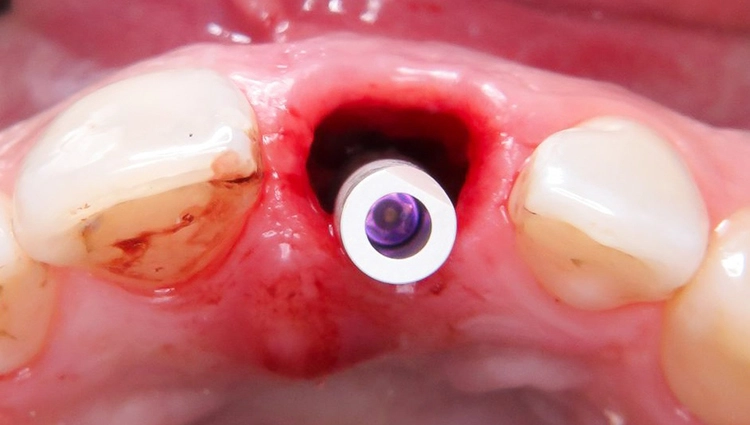

Chirurgischer Eingriff: Extraktion und Insertion

Unter Lokalanästhesie wurde der beherdete Zahn 21 extrahiert und hierbei auf die maximale Schonung der vestibulären Lamelle geachtet. Die Entzündung konnte rückstandslos entfernt werden. Die Sondierung ergab eine intakte faziale Knochenlamelle (Abb. 6). Die frische Extraktionsalveole wurde als Implantatbett aufbereitet und das Implantat (BLX ø 4 mm, 14 mm) entsprechend der Planung dreidimensional im palatinalen Bereich der Alveole inseriert [3,6] (Abb. 7 und 8).